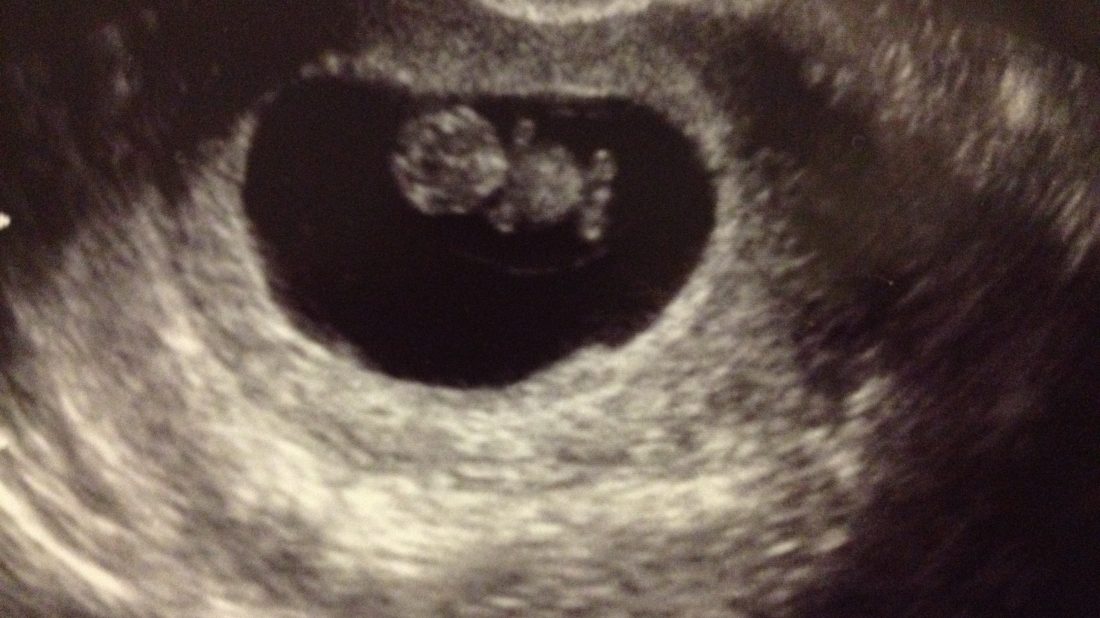

KLUB TĚHULEK! ELIŠKA Máme za sebou kontrolu srdíčka a podle slov paní doktorky je vše v pořádku. Vidět to malé stvoření, jak sebou kvedlá v té své bublině a přitom nic necítit, je opravdu zvláštní pocit. Hlavně to, jak vypadá je úžasný. Každý v něm vidí nějakou postavičku z pohádky, nebo nějaké zvířátko. Když jsem viděla, jak se tam vrtí, tak mi hrozně připomínal Jendu… přesně takhle se totiž vrtí po ránu v posteli, když se mu nechce z pelechu. V ten okamžik jsem byla přesvědčená o tom, že budeme mít chlapečka. 😉 Jen doufám, že nebude mít i stejné ranní nálady, kdy se minimálně půl hodiny na něj nesmí mluvit.